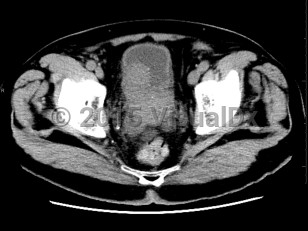

Prostate cancer

Most prostate cancers are identified at the local stage through annual screenings, and the majority of patients are asymptomatic at that stage. At later stages, physical findings may include perineal pain and urinary changes (eg, frequency, retention, nocturia). Urinary changes in men are more frequently the result of benign prostate conditions, which are sometimes found as comorbidities. Physical examination may reveal areas of induration, asymmetry, and/or prostate nodule. Diagnosis is confirmed via prostate biopsy.